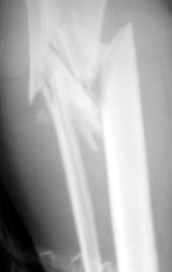

Рентгенограмма при поступлении. Думаю на ней видно распространение линии перелома вниз